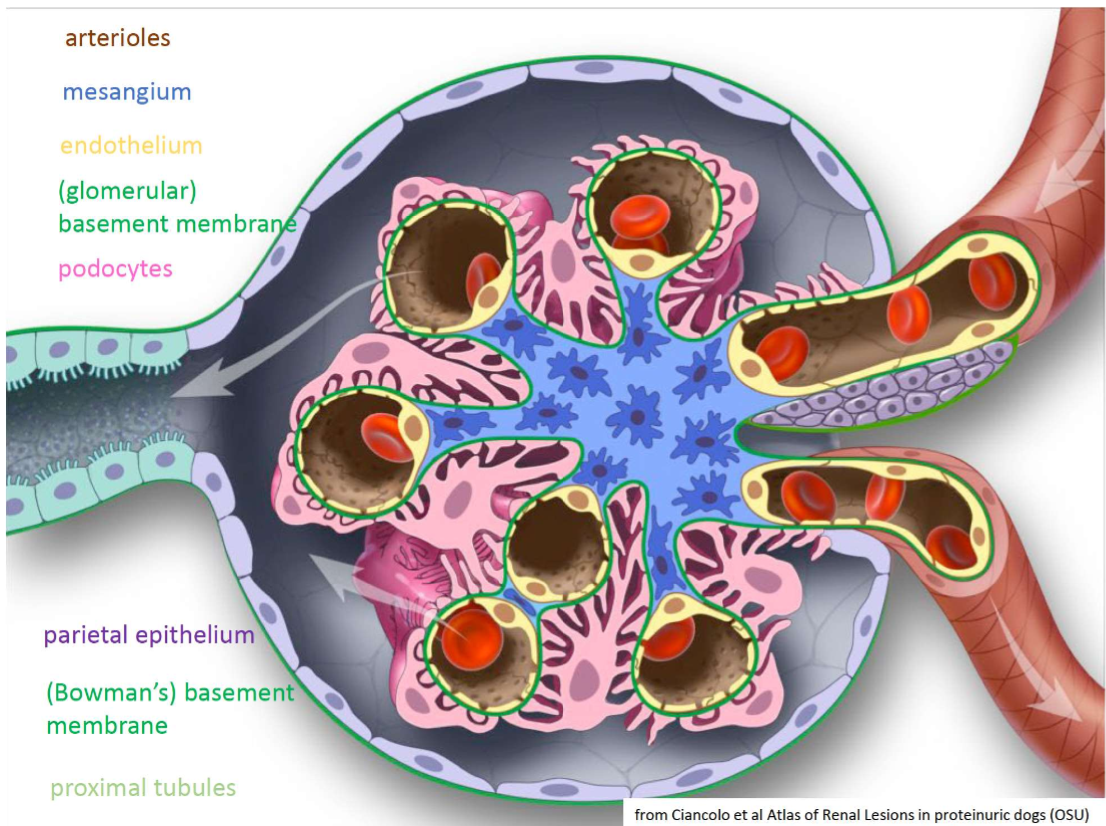

What is the structure of a Renal Corpuscle

What makes up the glomerular filtration barrier?

A

• Fenestrated capillary endothelium

• Basement membrane (produced by epi and endo cells)

• Podocytes (visceral epithelium)

• NB filtration is a function of size and charge

What is the Bowman’s capsule?

• Sac enclosing each glomerulus and forming the uriniferous space (filtrate)

• Has:

• Basement membrane

• Parietal epithelial cells